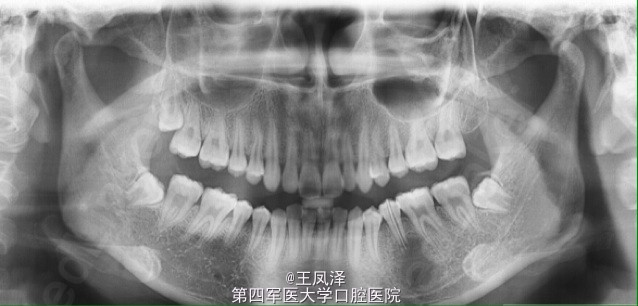

罕见巨型根尖囊肿一例(配清晰图和治疗过程)

患者,女,20岁,主诉:要求牙齿换药。现病史:因半年前下后牙咬合疼痛,在当地医院口腔科就诊,经多次换药,治疗未结束,现患者来到本地,遂来诊。